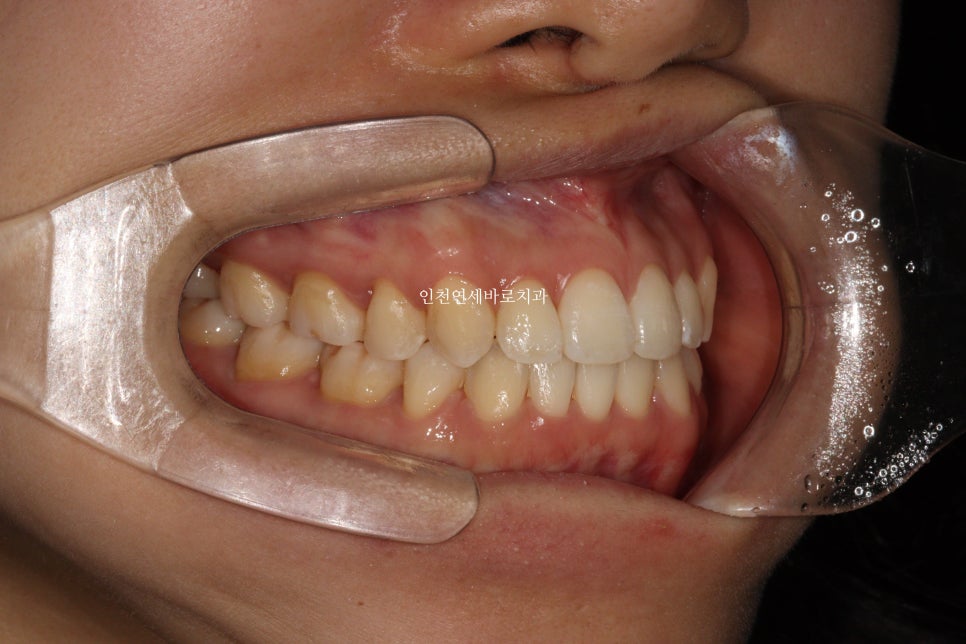

선천적결손치아가 있던 환자분이며, 웃을때 사진을 보면 약간의 비대칭도 관찰됩니다.

아래 앞니가 없다보니 중심선도 안맞고, 아래 치아의 사이즈도 양쪽이 다름을 알 수 있습니다.

비대칭이 있다보니 위쪽 치아가 전체적으로 기울어져 있는것도 확인됩니다.